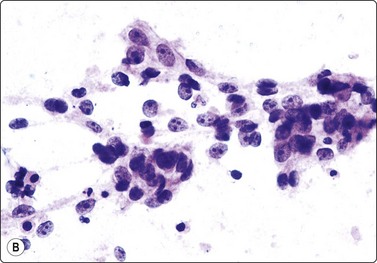

Acinic cell carcinoma (Figs 4.48-4.50)129,130

image image

Fig. 4.48 Acinic cell carcinoma

Epithelial fragments composed of cells with abundant vacuolated cytoplasm and relatively bland nuclei, resembling normal acinar cells; many naked nuclei; scanty, thin fibrovascular stroma. Note absence of well-formed acinar structures (A, MGG, IP; B, Pap, HP).

image

Fig. 4.49 Acinic cell carcinoma

Cells with oncocyte-like cytoplasm, distinction from oncocytoma difficult (MGG, HP).

Fig. 4.50 Acinic cell carcinoma

A less well-differentiated tumor may be difficult to type as acinic cell carcinoma. Ancillary techniques such as EM may help (MGG. HP).

Criteria for diagnosis

Abundant cell material with a clean background,

Cells mainly in clusters, scanty inconspicuous fibrovascular stroma,

Microacinar groupings,

Abundant, fragile, finely vacuolated, occasionally dense oncocyte-like cytoplasm,

Rounded, medium-sized nuclei, mild to moderate anisokaryosis, bland chromatin,

Many stripped nuclei.